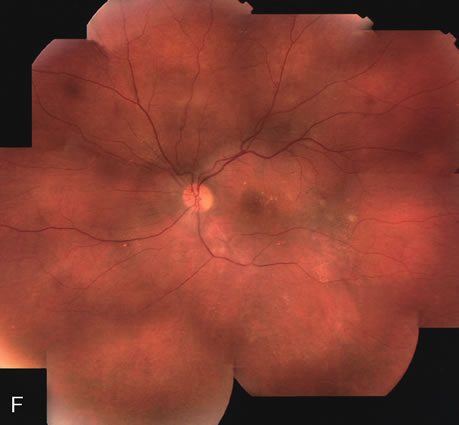

Clinically discernible peripheral dependent bullous neurosensory detachments have been described in patients with chronic CSC.85–92 Yannuzzi and co-workers first characterized the presence of RPE atrophic tracts extending inferiorly in the fundus periphery secondary to antecedent retinal detachment in patients with CSC.85 Presumably, there is a particularly severe and/or longstanding leakage of fluid from an RPE defect in the subretinal space at the posterior pole. The subretinal fluid gravitates inferiorly to form a dependent neurosensory detachment in a “flask,” “teardrop,” “dumbbell,” or “hourglass” pattern (Fig. 31). Sometimes the tract of subretinal fluid connecting the macular detachment with the bullous neurosensory detachment in the inferior hemisphere is so shallow that it is very difficult to appreciate. The RPE under the chronic retinal detachment experiences atrophic changes that appear as atrophic RPE tracts connecting the posterior pole with the dependent retinal detachment. The retina itself develops secondary manifestations including pigment migration, capillary dilatation (telangiectasia) proximally and capillary nonperfusion (ischemia) distally to the area of detached retina (see Fig. 31). The changes in the RPE consist of both RPE atrophy and pigment clumping in the form of perivascular deposits or bone spicules, a condition described by Gass as a “pseudoretinitis pigmentosa–like atypical CSC presentation.”87

Fig. 31. A 47-year-old woman with an18-year history of central serous chorioretinopathy in both eyes. A. Color photograph composite of the left eye shows bullous dependant detachment of the neurosensory retina inferiorly. B. Fluorescein angiogram composite reveals diffuse decompensation of the retinal pigment epithelium, multiple scattered pigment epithelium detachments 9PEDs), and obliteration of the retinal capillaries in the region of the detachments. Note the presence of early neovascularization at the junction between perfused and non-perfused retina. C. Clinical photograph of the left eye shows PED superior to the optic disc partially surrounded by fibrin deposits. D. Fluorescein angiography confirms the presence of active leakage from the serous PED. E, Color photograph composite of the same eye 2 months after laser treatment of the site of leakage reveals partial resolution of the detachment and lipid precipitation. F. Clinical photograph composite 16 months after the laser treatment in the area of the leakage shows complete resolution of the detachment and partial reperfusion of the inferior retina.